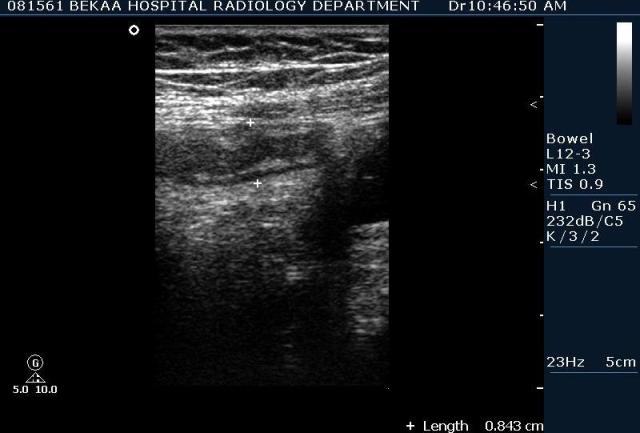

Диагностика острого аппендицита по УЗИ: очень актуальная тема; УЗ аппараты практически есть во всех клиниках; метод доступный и не сложный; главное владеть правильной техникой. Не буду загружать лишней теорией и разными ссылками; поделюсь практическим опытом. У меня линейный датчик 3-12 мегагерц с плавающей частотой; аппарат Филипс HD 11, всегда включаю соно-КТ (9800 цифровых каналов) и гармонику когда смотрю кишечник. Нормальный аппендикс видеть можно; но вопрос зачем??? Как правило, если при наличии достаточного опыта аппендикс не виден; значит скорей всего аппендицита нет. Когда "идешь" на аппендицит то главное по началу набраться терпения и......хорошая компрессия! По началу надо минут 10-15; потом когда появится достаточный опыт; за 2-5 минут можно справится и получить отличную визуализацию. Мочевой пузырь лучше опорожнить; часто он приподнимают тонкий кишечник и может закрыть "окно" через которое будет видно апендикс. Сначала находим слепую кишку потом находим илео-цекальное соединение;

после начинаем производить хорошую компрессию датчиком попрося пациента сообщить в какой точке боль наиболее выражена; медленными движениями датчика сканируем область наибольших болевых ощущений и как правило находим утолщенный отросток. Лучше начинать с поперечной визуализации и идти к верхушке аппендикса что бы убедится что это аппендикс и он заканчивается, а не тонкая кишка (которая если и закончится то только переходя в слепую); потом надо аккуратно развернуть продольно датчик и посмотреть от верхушки аппендикса к слепой. Норма диаметра: 3-4 мм; 5-6 мм под вопросом (клиника решает; но я в катаральный аппендицит не верю); 7-8 мм и больше, не компремируемый (фиксированный отросток)-острый аппендицит! Помимо наличие утолщенного аппендикса; признака "бычьего глаза" (bull-eye sign) при поперечном сканировании; надо обращать внимание на присуствие аппендоколитов в просвете; деструкцию стенки и свободной жидкости в зоне интереса.